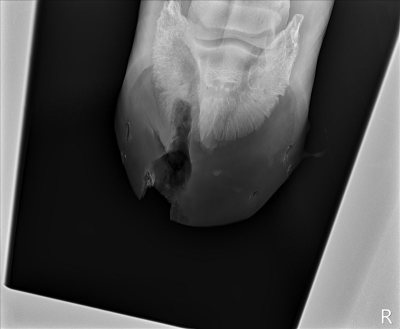

![]() |

| After surgery, with the hole and the missing coffin bone area. Not too bad, actually – there’s still bone in the middle, they didn’t take a clear slice out. |

| Side view of same. You can see the hole going up to the toe, and the scraping from both the top and bottom. |